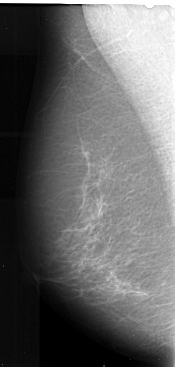

ics_version 1.0 filename A-1021-1 DATE_OF_STUDY 18 11 1993 PATIENT_AGE 59 FILM FILM_TYPE REGULAR DENSITY 2 DATE_DIGITIZED 6 1 1998 DIGITIZER DBA 21 SEQUENCE LEFT_CC LINES 5401 PIXELS_PER_LINE 2641 BITS_PER_PIXEL 16 RESOLUTION 42 NON_OVERLAY LEFT_MLO LINES 5491 PIXELS_PER_LINE 2611 BITS_PER_PIXEL 16 RESOLUTION 42 NON_OVERLAY RIGHT_CC LINES 5236 PIXELS_PER_LINE 2521 BITS_PER_PIXEL 16 RESOLUTION 42 OVERLAY RIGHT_MLO LINES 5491 PIXELS_PER_LINE 2491 BITS_PER_PIXEL 16 RESOLUTION 42 OVERLAY |

FILE: A_1021_1.RIGHT_MLO.OVERLAY TOTAL_ABNORMALITIES 1 ABNORMALITY 1 LESION_TYPE MASS SHAPE ARCHITECTURAL_DISTORTION MARGINS SPICULATED ASSESSMENT 4 SUBTLETY 3 PATHOLOGY MALIGNANT TOTAL_OUTLINES 1 BOUNDARY |

FILE: A_1021_1.RIGHT_CC.OVERLAY TOTAL_ABNORMALITIES 1 ABNORMALITY 1 LESION_TYPE MASS SHAPE ARCHITECTURAL_DISTORTION MARGINS SPICULATED ASSESSMENT 4 SUBTLETY 3 PATHOLOGY MALIGNANT TOTAL_OUTLINES 1 BOUNDARY |